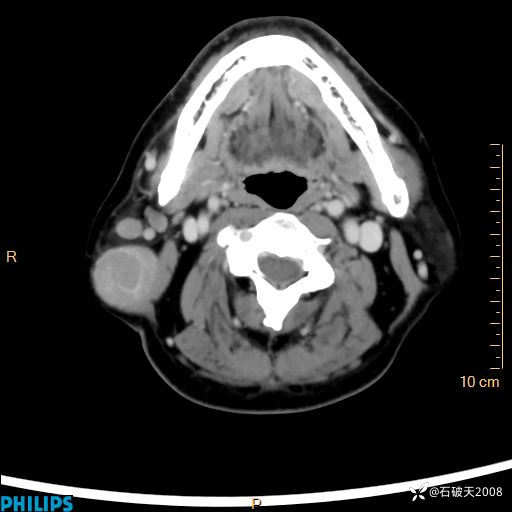

静脉期